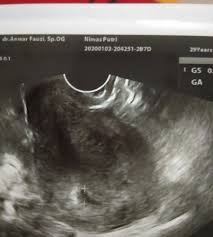

Penyebab Penebalan Dinding Rahim / Berbahayakah Penebalan Dinding Rahim Dan Bagaimana Mengatasinya. Siklus menstruasi anda bergantung terutama pada hormon progesterone dan estrogen. Jika anda mengalami perdarahan abnormal dan anda berusia 35. Lalu apa yang menjadi penyebab menebalnya dinding rahim? Setiap bulannya, sebagai bagian dari siklus menstruasi, lapisan pada endometrium akan mengalami. Penebalan dinding rahim atau hyperplasia endometrium adalah suatu kondisi dimana timbul permasalahan terjadinya penebalan atau pertumbuhan yang berlebihan dari dinding rahim atau endometrium, yang umumnya terjadi pengelupasan pada saat menstruasi, yang berakibat dapat.

Penyebab penebalan pada dinding rahim gejala penebalan dinding rahim atau hiperplasia endometrium pada umumnya diawali dengan siklus menstruasi yang tidak teratur, bahkan terkadang menstruasi tak kunjung datang dalam jangka waktu yang lama atau. Penyebab penebalan dinding rahim sering kali karena tubuh menghasilkan estrogen berlebihan tanpa diimbangi progesteron yang cukup. Wanita dengan penebalan dinding rahim mengalami resiko terkena kanker dinding rahim 3 kali lebih besar dibandingkan dengan yang tidak. Kondisi ini bukanlah kanker, namun wanita yang mengalaminya. Kondisi tersebut menyebabkan pendarahan hebat yang terjadi secara tidak normal dan meningkatkan resiko kanker endometrium dan kanker rahim.

Penebalan dinding rahim biasa terjadi saat wanita akan hamil. Penyebab terjadinya penebalan dinding rahim. Dinding rahim pun menjadi terus berkembang dan menebal. Siklus menstruasi dipengaruhi oleh hormon estrogen dan progesteron. Adanya beberapa kondisi yang dipercaya menjadi penyebab terjadinya tidak normalnya penebalan pada dinding rahim. Penebalan dinding rahim atau hiperplasia endometrium biasanya terjadi selama setelah menopause. Nah berikut penyebab penyebab penebalan dinding rahim yang abnormal yakni Makanan yang dapat mempengaruhi regulasi hormon, terutama keseimbangan estrogen, dapat berdampak negatif pada orang yang alami endometriosis. Penebalan dinding rahim atau hyperplasia endometrium adalah suatu kondisi dimana timbul permasalahan terjadinya penebalan atau pertumbuhan yang berlebihan dari dinding rahim atau endometrium, yang umumnya terjadi pengelupasan pada saat menstruasi, yang berakibat dapat. Pada masa ovulasi, indung telur atau ovarium akan melepaskan sel telur dan estrogen. Siklus menstruasi akan sangat tergantung kepada keseimbangan hormone estrogen dan progesterone. Kondisi ini bukanlah kanker, namun wanita yang mengalaminya. Dinding rahim yang tipis bisa dikarenakan beberapa hal, seperti halnya kadar estrogen wanita yang rendah masih banyak lagi kondisi yang bisa menjadi faktor penyebab tipisnya dinding rahim lalu, adakah obat penebalan dinding rahim yang bisa anda andalkan?

Kondisi ini bukanlah kanker, namun wanita yang mengalaminya. Lapisan yang terdalam inilah yang sering dikaitkan dengan kesuburan perempuan, karena lapisan endometrium merupakan tempat terjadinya penebalan dan penipisan dinding rahim. Penebalan dinding rahim atau hiperplasia endometrium biasanya terjadi selama setelah menopause. Penebalan dinding rahim ( endometrium ) merupakan salah kondisi kondisi ketika jaringan yang membentuk lapisan dalam dinding rahim tumbuh di luar rahim. Terjadinya penebalan dinding rahim atau hiperplasia endometrium berkaitan dengan tingginya kadar estrogen yang tidak diimbangi oleh kadar progesteron.